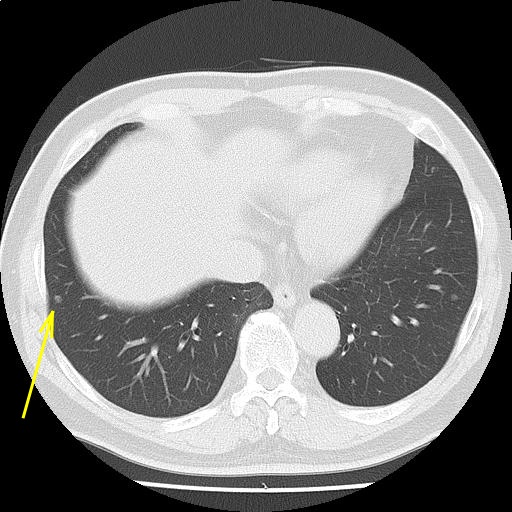

両肺下葉に小結節を認める。前回検査と比較して著変はなく、その他の肺野に明らかな異常所見を認めない。

陳旧性炎症性変化が疑われるが、経過観察を検討されたい。

縦隔リンパ節腫大を認めない。胸水を認めない。

両下葉に小結節を認める。経過観察をご検討されたい。